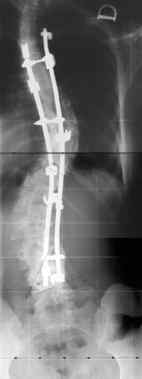

La paziente viene sottoposta a intervento chirurgico di artrodesi vertebrale posteriore con strumentazione all’età di 15 anni. Incisione da D2 a L5. Si incidono i piani sottocutanei, secondo la tecnica abituale si schelatrizzano le apofisi spinose, le lamine e le traverse. Si aprono tutte le articolazioni che vengono cruentate ad una ad una. Si prepara lo strumentario in relazione al piano strategico pre-operatorio preparato sulla radiografia in antero-posteriore, in bending test e al test di trazione. A sinistra del rachide vengono applicati 5 uncini e a destra 5. Si applicano le due barre di stabilizzazione; si ottiene la correzione ottimale della curva scoliotica e si appongono due strumenti a solidarizzare le barre. Si effettua un controllo rx intraoperatorio. Sutura per strati. Medicazione.

A controllo clinico a distanza di un anno la paziente sta bene, non ha avuto alcun problema; il rachide conserva una buona motilità; il controllo radiografico dimostra una buona stabilizzazione del rachide.